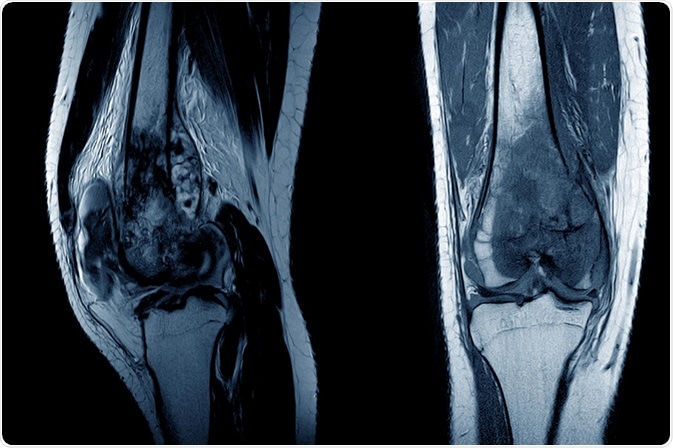

MRI of a knee joint showing osteosarcoma. Image Credit: April stock / Shutterstock.com